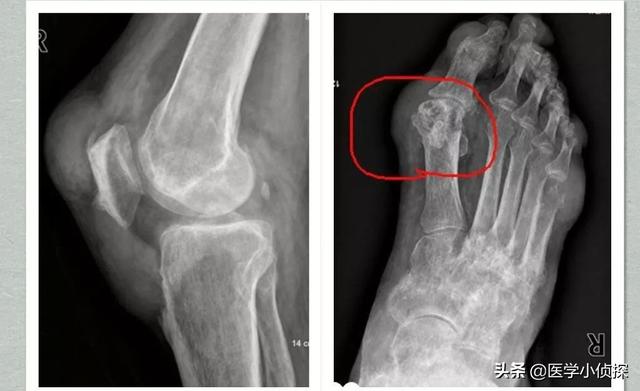

La deuxième étape consiste à effectuer une étude d'imagerie, par exemple pour détecter un "signe de double piste" sur l'échographie ou pour effectuer un "signe de double piste" sur l'échographie.La tomodensitométrie à double énergie révèle des dépôts d'urateetc., puis ouLes radiographies révèlent un gonflement des tissus mous, une destruction des bords du cartilage et une irrégularité des surfaces articulaires.!

La goutte peut être détectée par imagerie, la présence de cartilage articulaire "signe de double piste", l'épanchement articulaire, l'érosion osseuse, etc., peuvent également être diagnostiqués par des indicateurs de la fonction rénale.

- (10) Tuméfaction intra-articulaire asymétrique (confirmée par radiographie)

- (11) Kyste sous-cortical de l'os sans érosion osseuse (confirmé par radiographie)